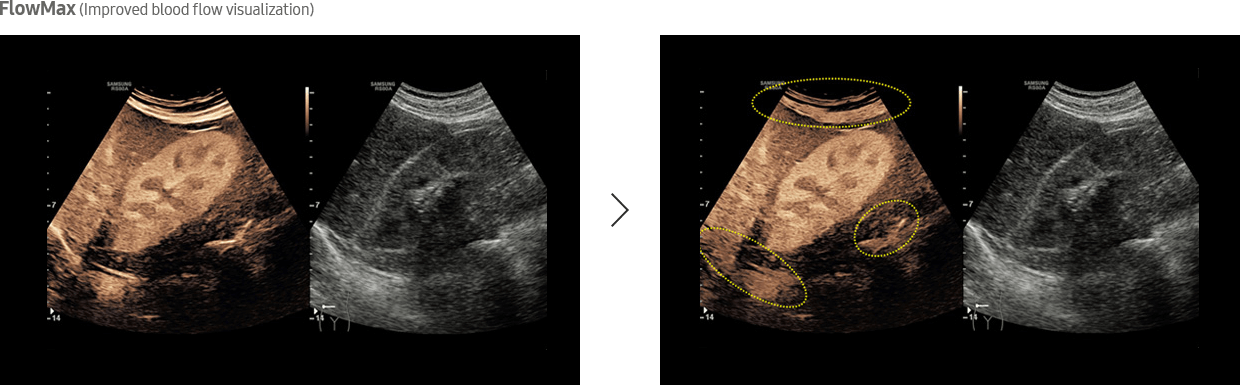

Designed for Advanced Lesion Diagnosis

CEUS+ technology, when stimulated with low MI frequencies, generate oscillating microbubbles that reflect both basic frequencies and harmonic signals. In addition, VesselMax and FlowMax allow for a clear visualization of vessels and blood flow so that you can form an informed, reliable diagnosis with confidence